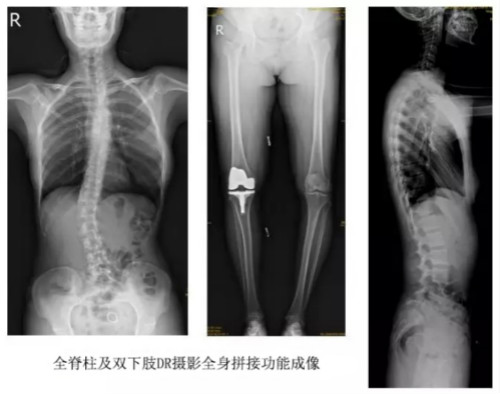

临床在诊治脊柱及下肢畸形时,往往采取矫正手术治疗。这就需要在对其进行手术前后,拍摄全脊柱或全下肢的X光片作为诊治依据,以便分析病情、制定手术方案和评估术后疗效。目前大部分医院使用的DR摄片机,因拍摄幅面受限,最大规格43cm,但成人的全脊柱长度一般约60cm,而全下肢更长,不能一次性拍摄出完整的全脊柱或全下肢的X光影像。以全脊柱摄片为例,各拍摄一张传统的颈椎、胸椎、腰椎的X片虽然就能观察到每个部位局部的侧弯情况,但不能观察到三者之间的连续性。因此传统X光片在这类疾病诊断上存在着一定的缺陷,无法更精准有效地进行临床诊断和治疗。

以某院所摄X光片为例,对比传统摄片与全身拼接功能的区别:

传统X光片只能观察每个部位的局部情况,无法在统一体上进行连续、全面的观察,全脊柱及下肢全长片则能直观的看到整体形变。通过DR全身拼接功能实现的完整成像,为诊治脊柱及下肢畸形提供了完美的临床影像依据,对临床诊断、术前手术方案的制定和术后疗效的评估等临床应用具有十分重要的意义,有效满足了此类疾病临床诊断和治疗的要求。